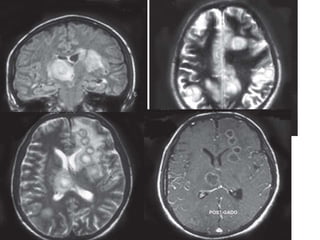

CECT axial scans of the cranium showing a large ring

enhancing lesion with smooth thin walls in a left parafalcine location with

extensive vasogenic edema causing effacement of the ipsilateral frontal

horn and midline shift to the contralateral side. Adjacent smaller enhancing

rings are also seen in another case—brain abscess with daughter

abscesses